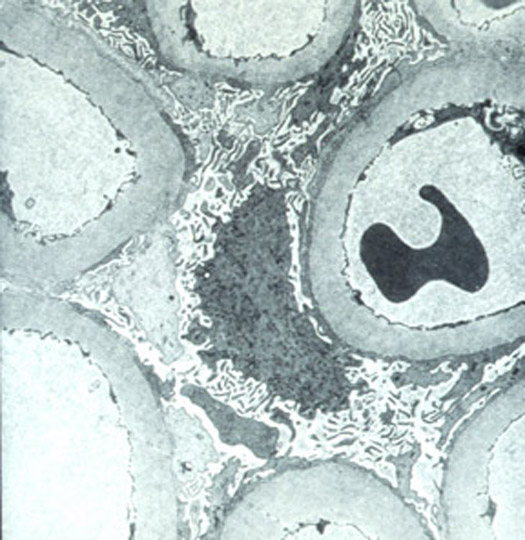

Acute hyperoxalemia produces calcium oxalate crystal deposition in tubular lumina, the crystals are irregular, laminates or in fan form; they are colourless with routine stains and birefringent with polarized light. Chronic lesions relate to tubular basement membranes rupture and interstitial deposits with inflammatory reaction and fibrosis. These crystals are conserved in the tissue routinely processed (Figure 14).

Figure 14. Nephrectomy of renal allograft by chronic rejection. There are extensive deposits of oxalate with variable size and form; they occupy mainly distal tubules and, in fewer amounts, they can be seen in the interstitium, with gigantocellular reaction. The asterisks indicate proximal tubules, which usually do not contain these crystals. This finding, thus severe, does not indicate oxalosis; there are frequent and unspecific deposits in cases of renal failure in native or transplanted kidneys. (H&E seen with polarized light, X200).